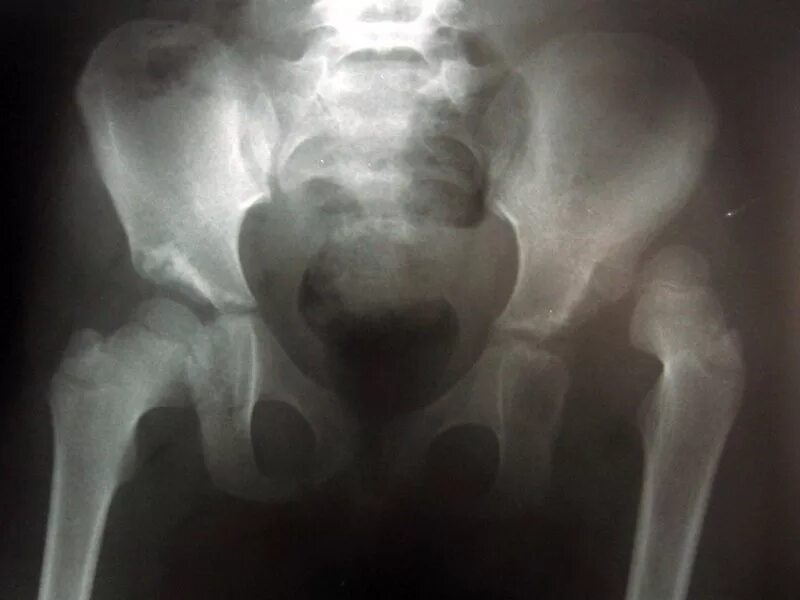

Вывих тазобедренного у взрослых